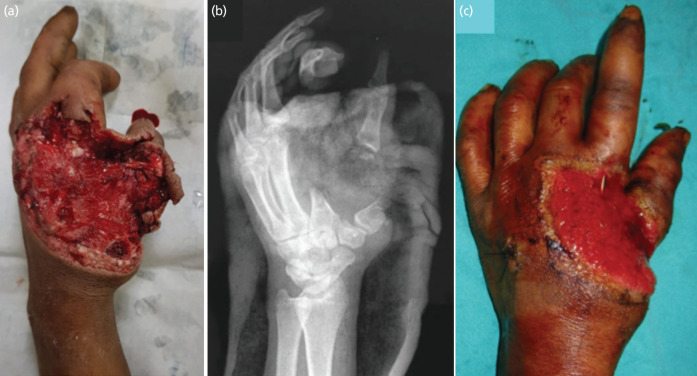

Free fibula flap has been a workhorse for head, neck, and extremity long bone defects. We discuss the reconstruction challenge in an unusual hand injury case involving the loss of multiple metacarpals and soft tissue with surprising preservation of finger vascularity. The reconstructive goals were addressed with a microvascular osteocutaneous fibula flap transfer with multiple osteotomies to create spitting images of metacarpals and soft tissue defects restored with the skin paddle. The outcome, in terms of functional gain, was sufficient for managing day-to-day activities. We share our experience in reconstructing this unique presentation of a complex hand injury.